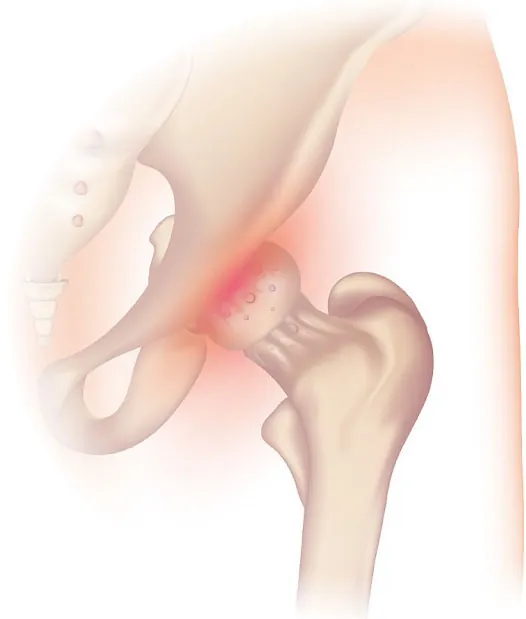

• a bony projection that develops along bone edges, known as a bone spur (Figure 13.7); and

X-ray of bone spur, labeling Calcaneus (Heel Bone) and Heel Spur

Figure 13.7 This x-ray image shows a bone spur that has developed on the heel of the foot. (credit: “Achilles insertional calcific tendinosis” by Mikael Haggström/Wikimedia Commons, CC0)